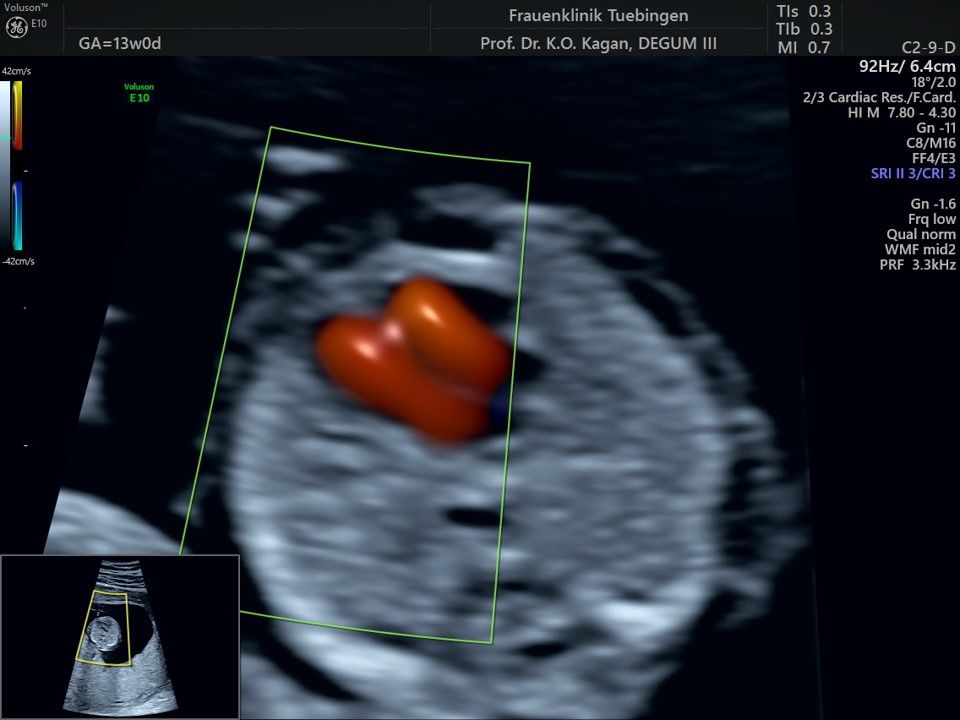

Im Rahmen des Ersttrimester-Screenings untersuchen wir die Organe des Feten mittels Ultraschall. Dabei machen wir auch gerne ein Bild für Sie.

Obwohl der Fet zu diesem Zeitpunkt erst zwischen 5 und 8cm groß ist, lassen sich bereits etwa die Hälfte aller schwerwiegenden Fehlbildungen erkennen bzw. ausschließen. Sollten wir eine Auffälligkeit sehen, werden wir mit Ihnen den Befund und das weitere Vorgehen ausführlich besprechen.

Herz